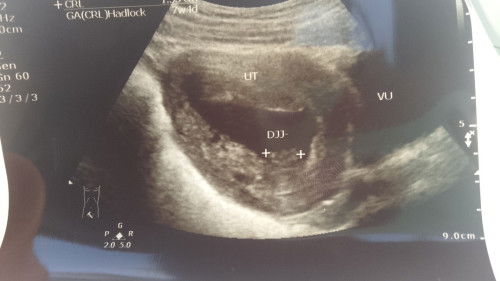

Assalamualaikum bunda2 usia kehamilan 8 minggu 2 hari ,sering mual sampe muntah ,sering pusing serasa muter😵💫 .yg paling ga enak itu mual smpe keluar semua bun kalo abis d isi . Apa ada yg sama ngalamin kaya gini ga ? Kalian mnum vitamin apa aja bun buat menangani nya #mohonbantujawabbunda